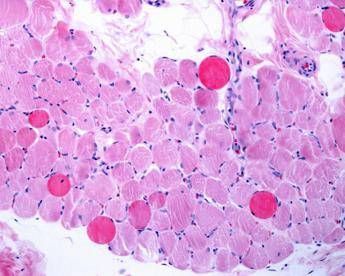

(Adnkronos) – Sono positivi i risultati di un’analisi dei dati a lungo termine – comprese le prime valutazioni dello studio multicentrico in aperto Guardian, attualmente in corso – che valuta Agamree* (vamorolone) in pazienti affetti da distrofia muscolare di Duchenne (Dmd). Lo annuncia in una nota Santhera Pharmaceuticals, precisando che l’analisi ha incluso pazienti mai trattati con corticosteroidi e che hanno iniziato il trattamento con Agamree tra i 4 e i 7 anni di età nell’ambito di studi clinici, proseguendo poi attraverso vari programmi di accesso tra cui lo studio Guardian.

Sono stati analizzati i dati di un massimo di 110 pazienti, con un numero variabile in base alla disponibilità delle informazioni. In questa analisi i pazienti avevano ricevuto il trattamento per un massimo di 8 anni, con un follow-up mediano di circa 5 anni. La maggior parte dei pazienti ha mantenuto dosi elevate (4-6 mg/kg/giorno) in contesti clinici di real world durante il periodo di osservazione. I risultati mostrano che i pazienti trattati con vamorolone hanno mantenuto la funzione motoria durante il follow-up prolungato, dimostrando un’efficacia duratura del trattamento misurata in base al tempo di perdita della deambulazione paragonabile a quella dei corticosteroidi standard (p=0,91). Nelle analisi di sottogruppi prestabilite non sono state osservate differenze rispetto al deflazacort o al prednisone assunti quotidianamente. I dati – riporta l’azienda – continuano a confermare un profilo di sicurezza e tollerabilità differenziato rispetto ai corticosteroidi tradizionali. I pazienti trattati con Agamree hanno registrato un tasso significativamente inferiore di fratture vertebrali (p=0,0061), hanno mantenuto una crescita normale senza il rallentamento osservato con i corticosteroidi standard (p